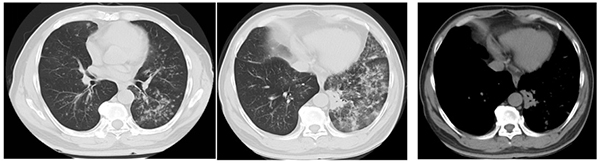

赵先生并无吸烟史,却有肺癌家族史(父亲患肺癌),这提示了遗传背景在肺癌发生中的潜在影响。2018年6月,他在外院的胸部CT提示双肺弥漫结节影,左肺斑片状实变影伴磨玻璃影,初步诊断考虑为“肺结核可能”。转至北京胸科医院结核科后,痰涂片中发现腺癌细胞,结核病相关检查均为阴性,2018年8月最终明确诊断为肺腺癌IV期。基因检测结果显示EGFR基因突变(为比较复杂的复合突变19-Del/T790M/20-Ins),这为后续靶向治疗提供了关键依据,也为患者带来了极大的希望。

治疗前(2018年6月)